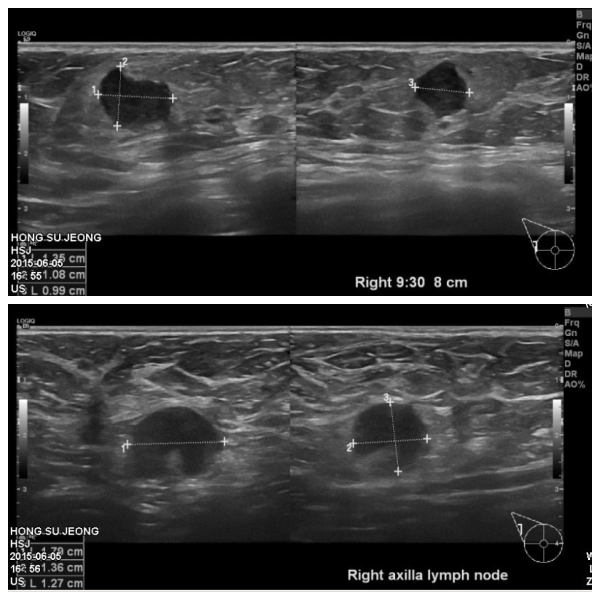

건강 검진상 이상 소견으로 내원하신 50대 여성분으로 우측 유방 9시 30분 방향에

유륜에서 8cm 떨어진 부위에 있는 혹 조직검사와, 겨드라이 림프절 비대 세포검사 시행

하여, 우측 침윤성 유관암과, 겨드랑이 전이 진단 되었습니다.